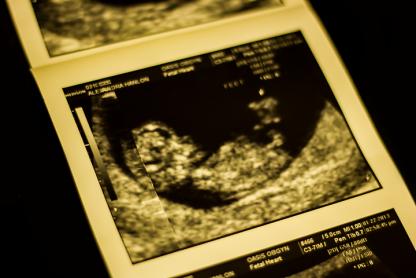

Attachment 8296Attachment 8297

Nub looks quite low and flat on first pic. Looks kind of boyish on the second pic and I don't think there is much in the skull theory.

If the second pic is more recent, I would say BOY..how far along r u in these scan pics?

I am 11+3

The photos were both done today!